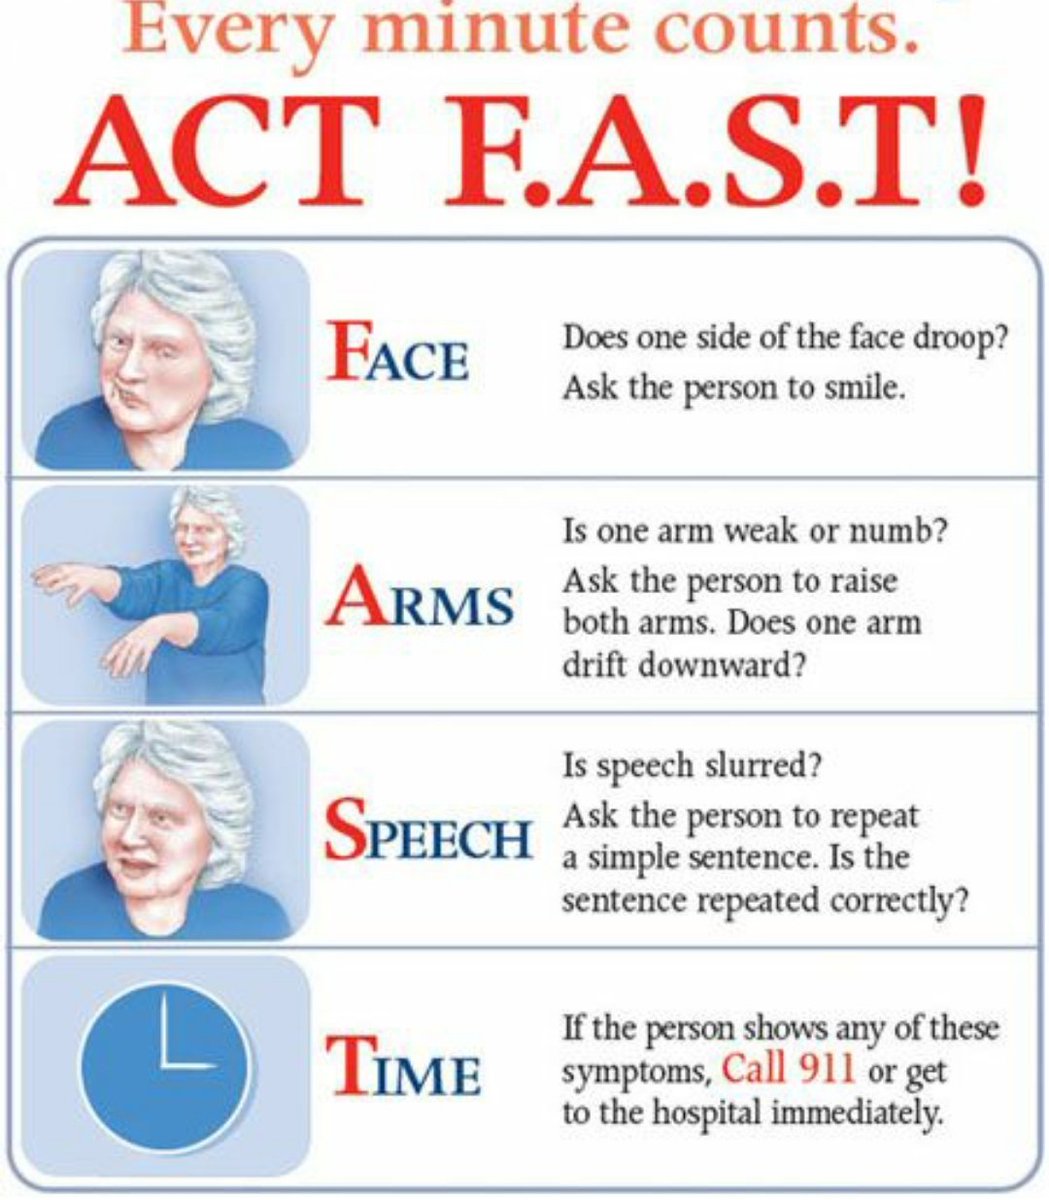

💥أعراض #السكته_الدماغيه بنوعيها

سر التشخيص كلمتين

🔑تغير #مفاجئ

🔑في #نتعاجل او #عاجل (الاعراض)

ن👁️نظر

ت🚶♂️توازن

ع🤐عسر في الكلام

ا😏انحراف في الفم والوجه

ج🦽جانب من الجسم لايتحرك او يحس

ل📞🚑لاتتردد

اتصل ب 911 واذهب لاقرب مركز متخصص

فيديو توعوي

كيف تتصرف إذا رأيت

💥احد أعراض #السكته_الدماغيه بنوعيها

المختصره في كلمه #نتعاجل او #عاجل

ن👁️نظر

ت🚶♂️توازن

ع🤐عسر في الكلام

ا😏انحراف في الفم والوجه

ج🦽جانب من الجسم لايتحرك او يحس

ل📞🚑لاتتردد اتصل ب 911 واذهب لاقرب مركز متخصص